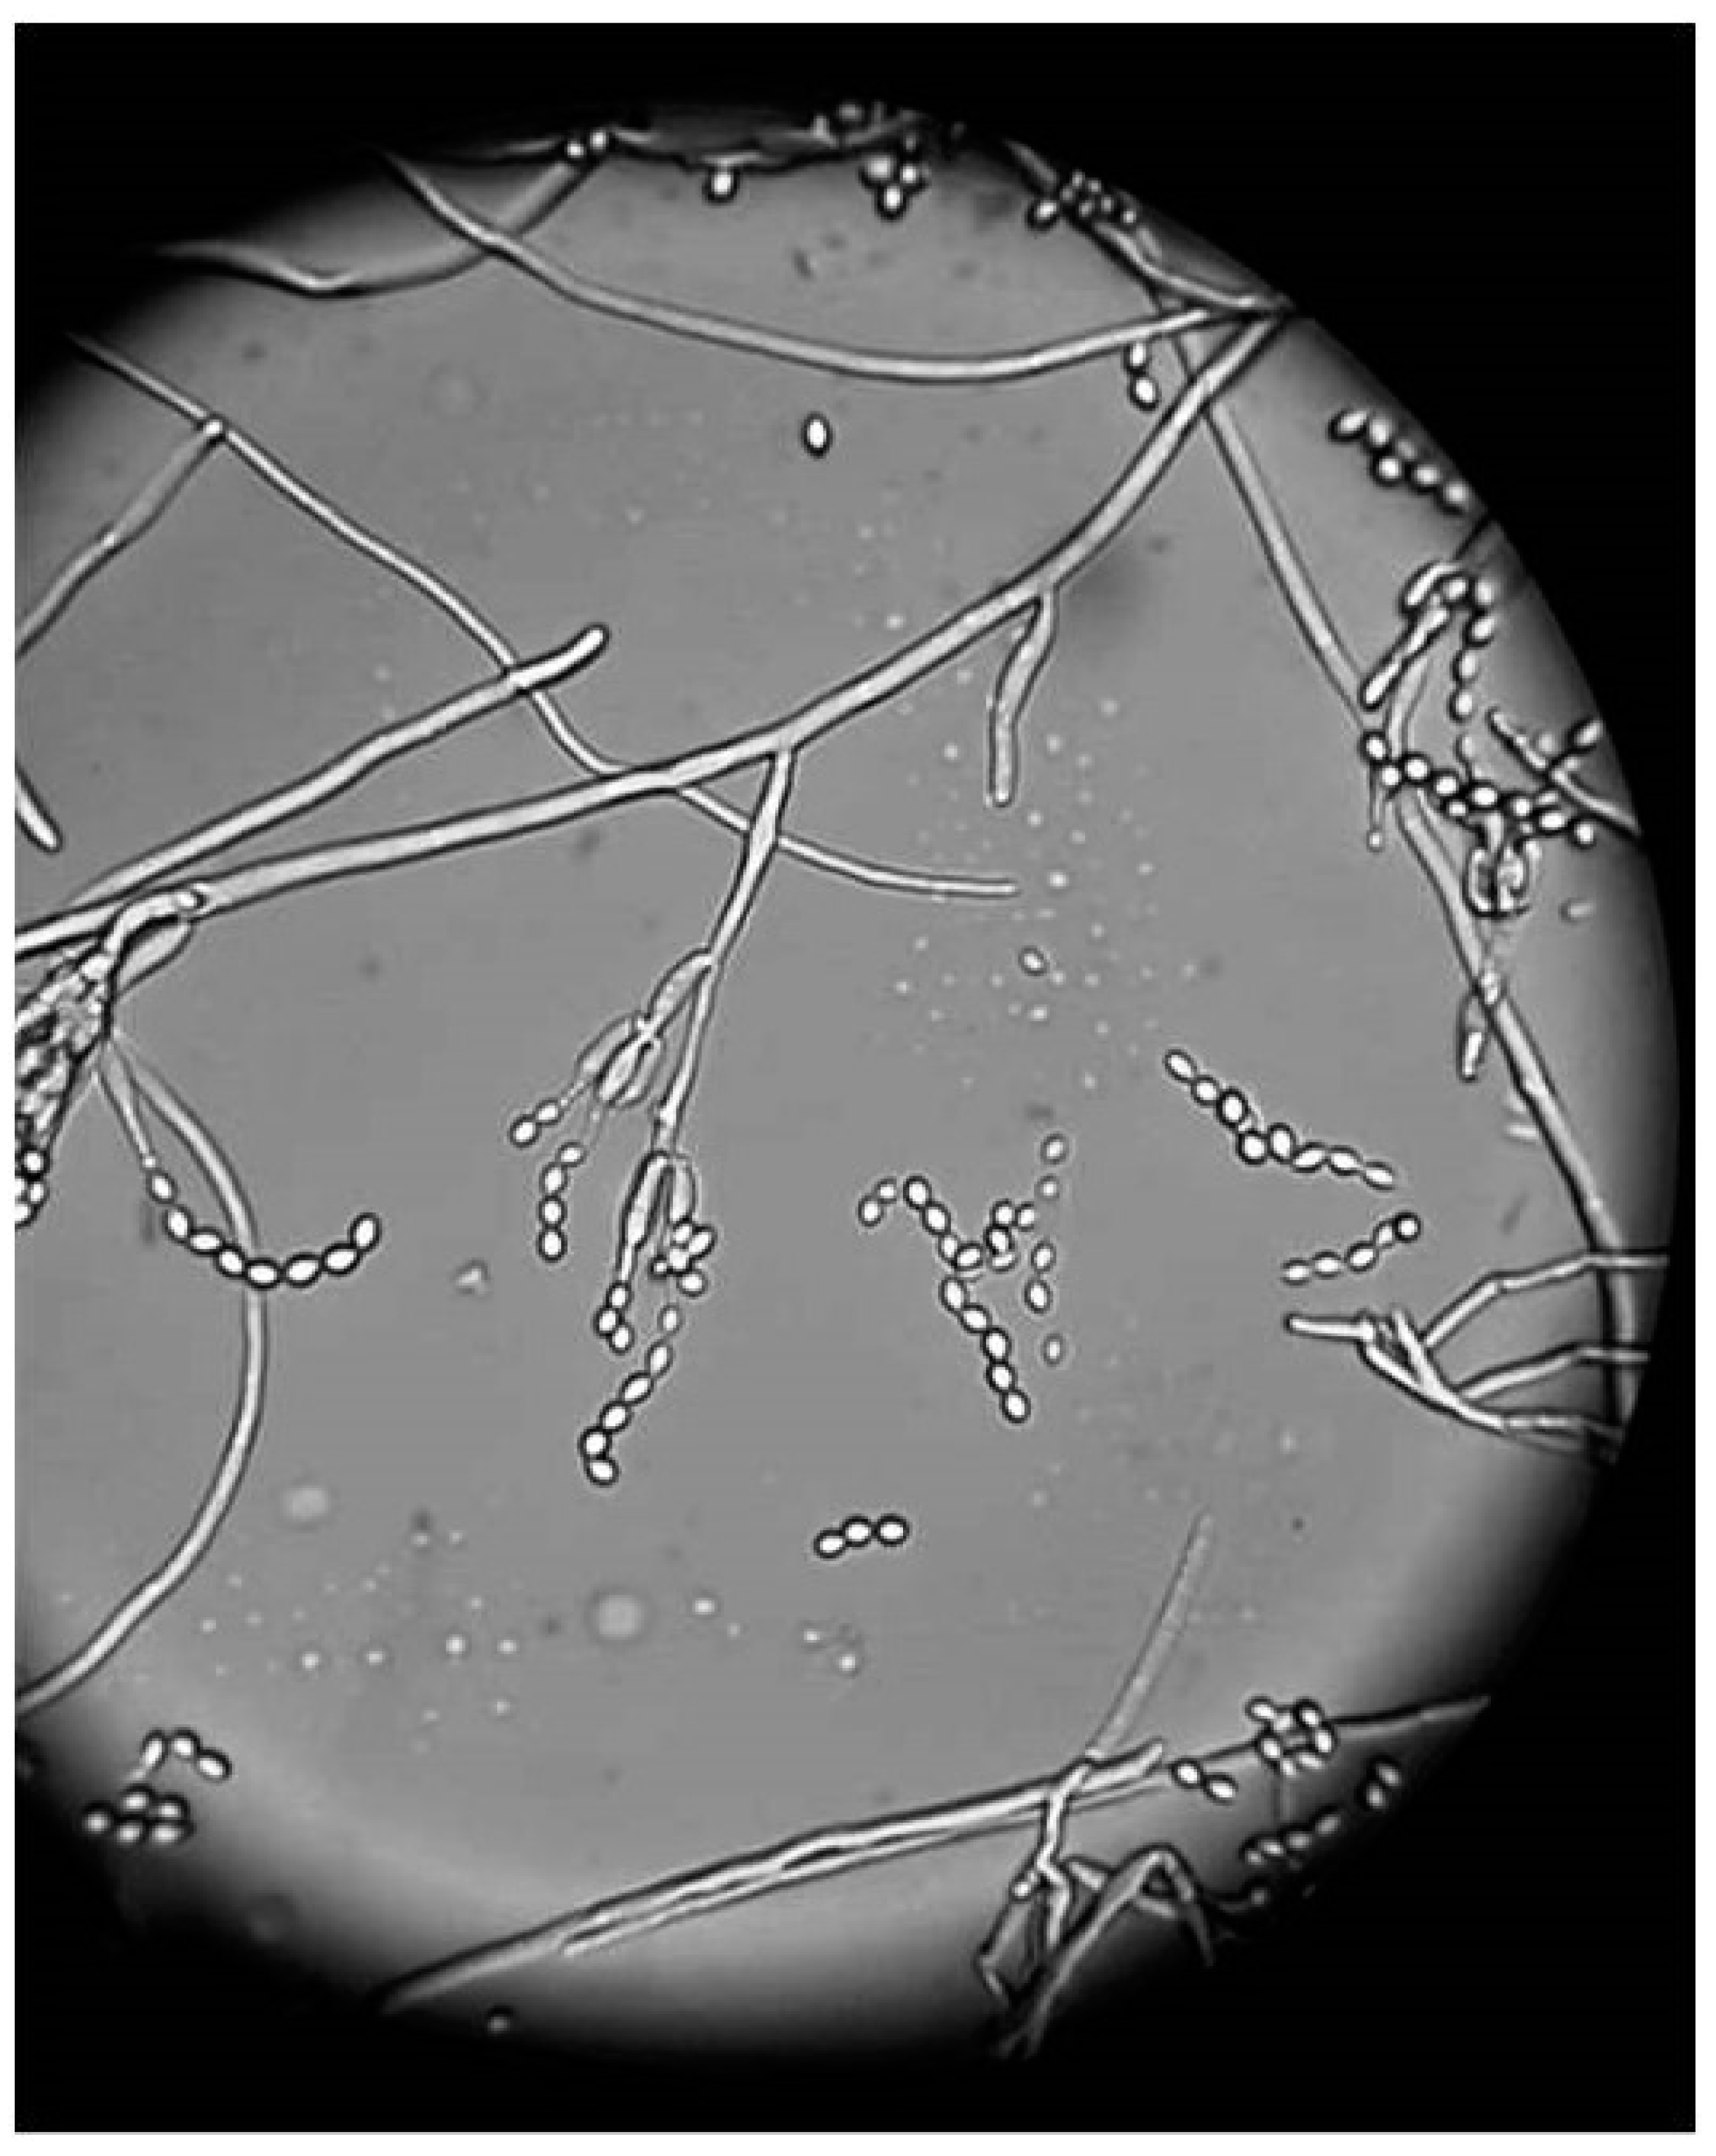

2.1. Culture

3. Results